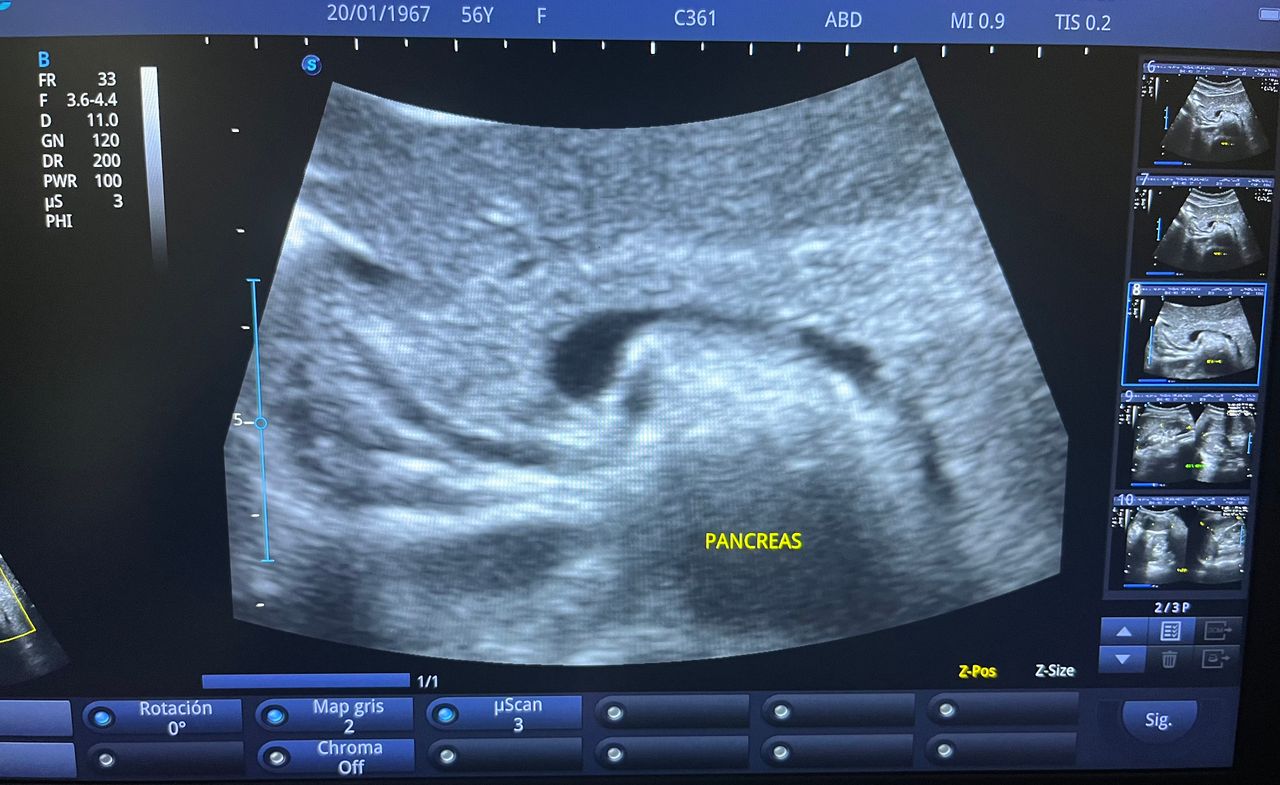

Médico general con 15 años de experiencia, master en enfermedades infecciosas y antibioticoterapia por parte de la Universidad Cardenal Herrera en Valencia, ademas de diversos diplomados en el área de Infectología y Parasitología, Urgencias, Imagenología y Medicina del Trabajo. He laborado en Hospitales y Clínicas en el área de Urgencias, en Laboratorios realizando estudios de Imagen, en especifico ultrasonidos de todo tipo desde básicos hasta avanzados incluidos los obstétricos estructurales, en Secretaría de Salud del Estado de Querétaro realizando ultrasonidos obstétricos para la detección de malformaciones en los tres trimestres del embarazo en diversos centros de salud, como médico de Empresas en el campo de Salud Laboral y actualmente en este consultorio en donde para su mejor atención y siempre buscando integrar la mayoría de las herramientas diagnosticas cuento con equipo de ultrasonido como apoyo en la exploración del paciente o como servicio diagnostico por imagen, realizo ultrasonidos convencionales (hepatobiliar (hígado, páncreas, vesícula y bazo), vías urinarias, ginecológico abdominal y transvaginal, tiroideo, prostático, testicular, pared abdominal) y especializados (dopler obstétrico en los 3 trimestres de embarazo), musculoesquelético en lesiones deportivas. También cuento con un equipo de electrocardiograma de 12 derivaciones para monitoreo completo del funcionamiento cardiaco, espirometria para evaluar la función pulmonar en la consulta, pruebas rápidas que se realizan en consultorio para detectar de forma mas precisa enfermedades infecciosas como Influenza A y B, covid19, infecciones urinarias, dengue, zika, chikungunya. Cuento con diversas vacunas para prevención de enfermedades. Siempre con el objetivo de dar el mejor servicio y atención a su salud. Lo espero en consulta para escucharlo y estudiar su caso de la forma más completa posible, estoy seguro de que tendremos las mejores opciones para su tratamiento. Mi tranquilidad es que usted se vaya con todas sus preguntas e inquietudes resueltas.

• Ultrasonido hepatobiliar

$800